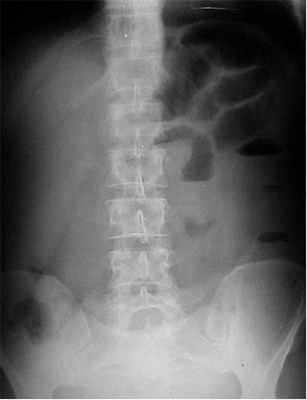

1. Рентгенологическое обследование является основным специальным методом диагностики ОКН. Обзорная рентгенография брюшной полости должна проводиться при малейшем подозрении на ОКН. При этом выявляется ряд признаков. В норме газ имеется в ободочной кишке. Появление газа в тонкой кишке указывает на непроходимость. Характер скопления газа в просвете кишечника различается при разных вариантах КН (рис. 1). Рисунок 1. Схема скопления газа в просвете кишечника при разных вариантах КН. а - высокая тонкокишечная непроходимость. Возможно наличие единичных горизонтальных уровней жидкости и газа. Наличие газа в толстой кишке не характерно Рисунок 1. Схема скопления газа в просвете кишечника при разных вариантах КН. б - низкая тонкокишечная непроходимость. Обычно видны множественные горизонтальные уровни жидкости и газа (чаши Клойберга). Наличие газа в толстой кишке не характерно Рисунок 1. Схема скопления газа в просвете кишечника при разных вариантах КН. в - странгуляционная кишечная непроходимость. Могут быть как единичные, так и множественные горизонтальные уровни жидкости и газа. Наличие газа в толстой кишке не характерно. Обычно по снимкам удается определить, петли какой кишки - тонкой, толстой или обеих - растянуты газом. При наличии газа в тонкой кишке хорошо видны спиралевидные складки слизистой оболочки (Керкринговы складки), занимающие весь поперечник кишки.

В тощей кишке они имеют вид круговой ребристости, напоминающей «скелет селедки» (симптом Кейcи), в подвздошной кишке - более редкие, прямые и толстые. При скоплении газа в толстой кишке видны гаустры, которые занимают лишь часть поперечника кишки [7, 9-12].

![]()

На рентгенограммах, полученных в положении стоя или лежа на боку, обычно видны горизонтальные уровни жидкости и газа (рис. 2). Рисунок 2. Обзорная рентгенограмма брюшной полости. Видны чаши Клойбера, уровни жидкости. Заполненные газом кишечные петли имеют вид опрокинутых чаш (чаши Клойбера). Они появляются при странгуляции через 1-2 ч после начала заболевания, при обтурации - через 3-5 ч. По размерам чаш Клойбера, их форме и локализации можно судить об уровне непроходимости.

При тонкокишечной непроходимости чаши Клойбера небольших размеров, ширина горизонтального уровня жидкости больше, чем высота столба газа над ним. Обычно наблюдается большое количество горизонтальных уровней с изменением их расположения в течение времени и перемещением жидкости из одной петли в другую. Горизонтальные уровни жидкости ровные. На фоне газа хорошо видны складки слизистой оболочки (складки Керкринга), принимающие форму растянутой спирали.

При непроходимости тощей кишки горизонтальные уровни жидкости локализуются в левом подреберье и эпигастральной области. При непроходимости в терминальном отделе подвздошной кишки уровни жидкости расположены в области мезогастрия.

При тонкокишечной непроходимости, кроме чаш Клойбера, на рентгенограммах видны растянутые газом кишечные петли, принимающие форму «аркад» или «органных труб», похожих на перевернутые буквы J и U.

При толстокишечной непроходимости горизонтальные уровни жидкости расположены по периферии брюшной полости, в боковых отделах живота, и их меньше, чем при тонкокишечной непроходимости. Высота чаш Клойбера преобладает над шириной. На фоне газа видны полулунные складки слизистой оболочки («гаустры»). Уровни жидкости не имеют ровной поверхности («зеркала»), что обусловлено наличием в толстой кишке плотных кусочков кала, плавающих на поверхности жидкого кишечного содержимого.

При динамической паралитической непроходимости, в отличие от механической, горизонтальные уровни жидкости наблюдаются одновременно как в тонкой, так и в ободочной кишке. Перемещения кишечных уровней со временем из одного колена кишки в другое не наблюдается. При динамической спастической непроходимости по ходу тонкой кишки видны мелкие чаши Клойбера, расположенные цепочкой слева сверху вниз и вправо.